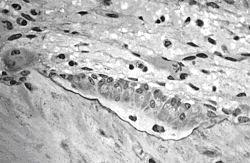

Los osteoblastos se disponen en el frente formador de hueso, en un capa epitelioide de células cuboideas o cilíndricas bajas.

El núcleo, con nucléolo único, está muy desarrollado, situado con frecuencia en el extremo de la célula más distante de la superficie ósea. Además contienen un aparato de Golgi.bien desarrollado, con numerosas mitocondrias, con abundante retículo endoplasmático rugoso que confiere un color intensamente basófilo al citoplasma.